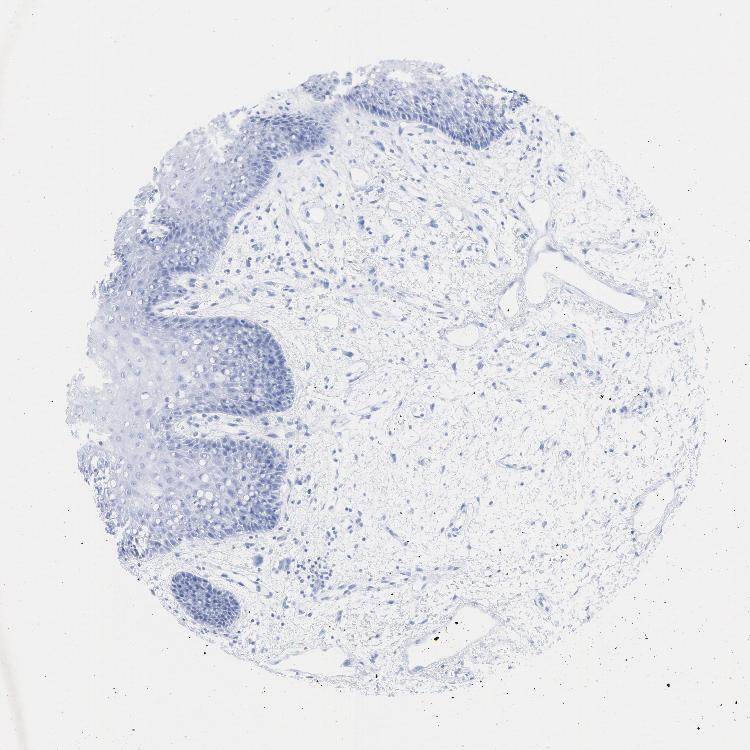

TISSUE PRIMARY DATA ORAL MUCOSA Show tissue menu

ORAL MUCOSA - Antibody stainingi

Antibody staining in the annotated cell types in the current human tissue is reported as not detected, low, medium, or high, based on conventional immunohistochemistry profiling in selected tissues. This score is based on the combination of the staining intensity and fraction of stained cells.

Each image is clickable and will lead to virtual microscopy that enables deeper exploration of all samples and also displays staining intensity scores, fraction scores and subcellular localization as well as patient and tissue information for each sample.

Antibody HPA052625Antibody CAB004300Antibody CAB004674

Squamous epithelial cells HighNot detectedLow